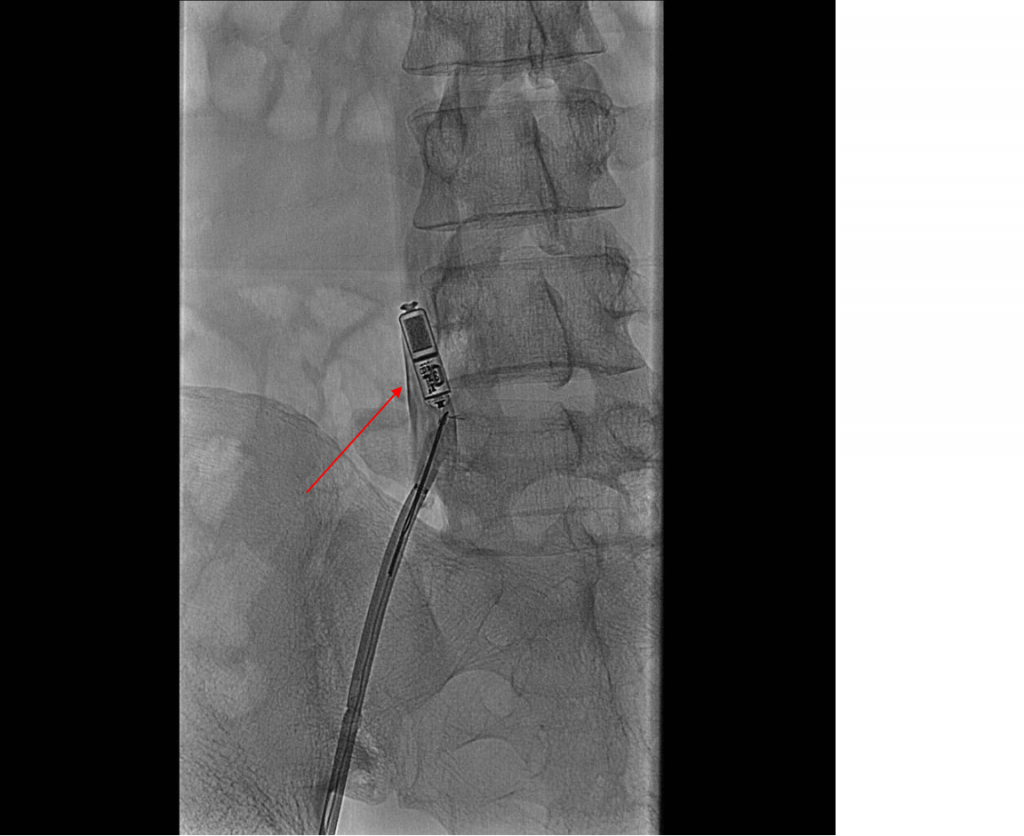

Před samotnou implantací byl pacient bez manifestního infekčního onemocnění, s nízkými markery zánětu. V souladu s protokolem implantace leadless kardiostimulátoru byl systém (Micra) po standardní přípravě femorální žíly zaveden do oblasti baze pravé komory. Stimulační práh po třetím testu stability byl 0,9 V při 0,40 ms, což bylo shledáno jako dostatečné a systém byl uvolněn. Třetí den od implantace byla telemetricky patrná neefektivní stimulace, při interogaci přístroje byl zjištěn vzestup stimulačního prahu na 3,6 V při 0,40 ms. Provedený rtg snímek hrudníku neprokázal dislokaci stimulátoru. Z důvodu trvající dependence pacienta na stimulaci byla z bezpečnostních důvodů zavedena dočasná transvenózní kardiostimulace. S cílem snížení stimulačního prahu bylo zahájeno podávání kortikoidů, bohužel však bez efektu. Sedmý den od výkonu byla již na rtg patrná dislokace stimulátoru do levé větve pulmonální arterie (obr. 1). Stimulátor byl prozatím ponechán in situ.

Obr. 1 – Skiagram hrudníku s dislokovaným leadless kardiostimulátorem (červená šipka)Jelikož byl pacient i nadále dependentní na kardiostimulaci, bylo rozhodnuto o zavedení epikardiálního stimulačního systému. Po provedení anterolaterální minithorakotomie byl systém implantován do oblasti horního epigastria, pod levý přímý břišní sval. Výkon samotný proběhl nekomplikovaně, ale několik dní po implantaci došlo k hnisavé sekreci z rány. Kultivačně byl prokázán Staphylococcus aureus. Opět byla nutná extrakce stimulačního systému, k dohojení rány bylo nutné použít uzavřený podtlakový drenážní systém (V.A.C.).